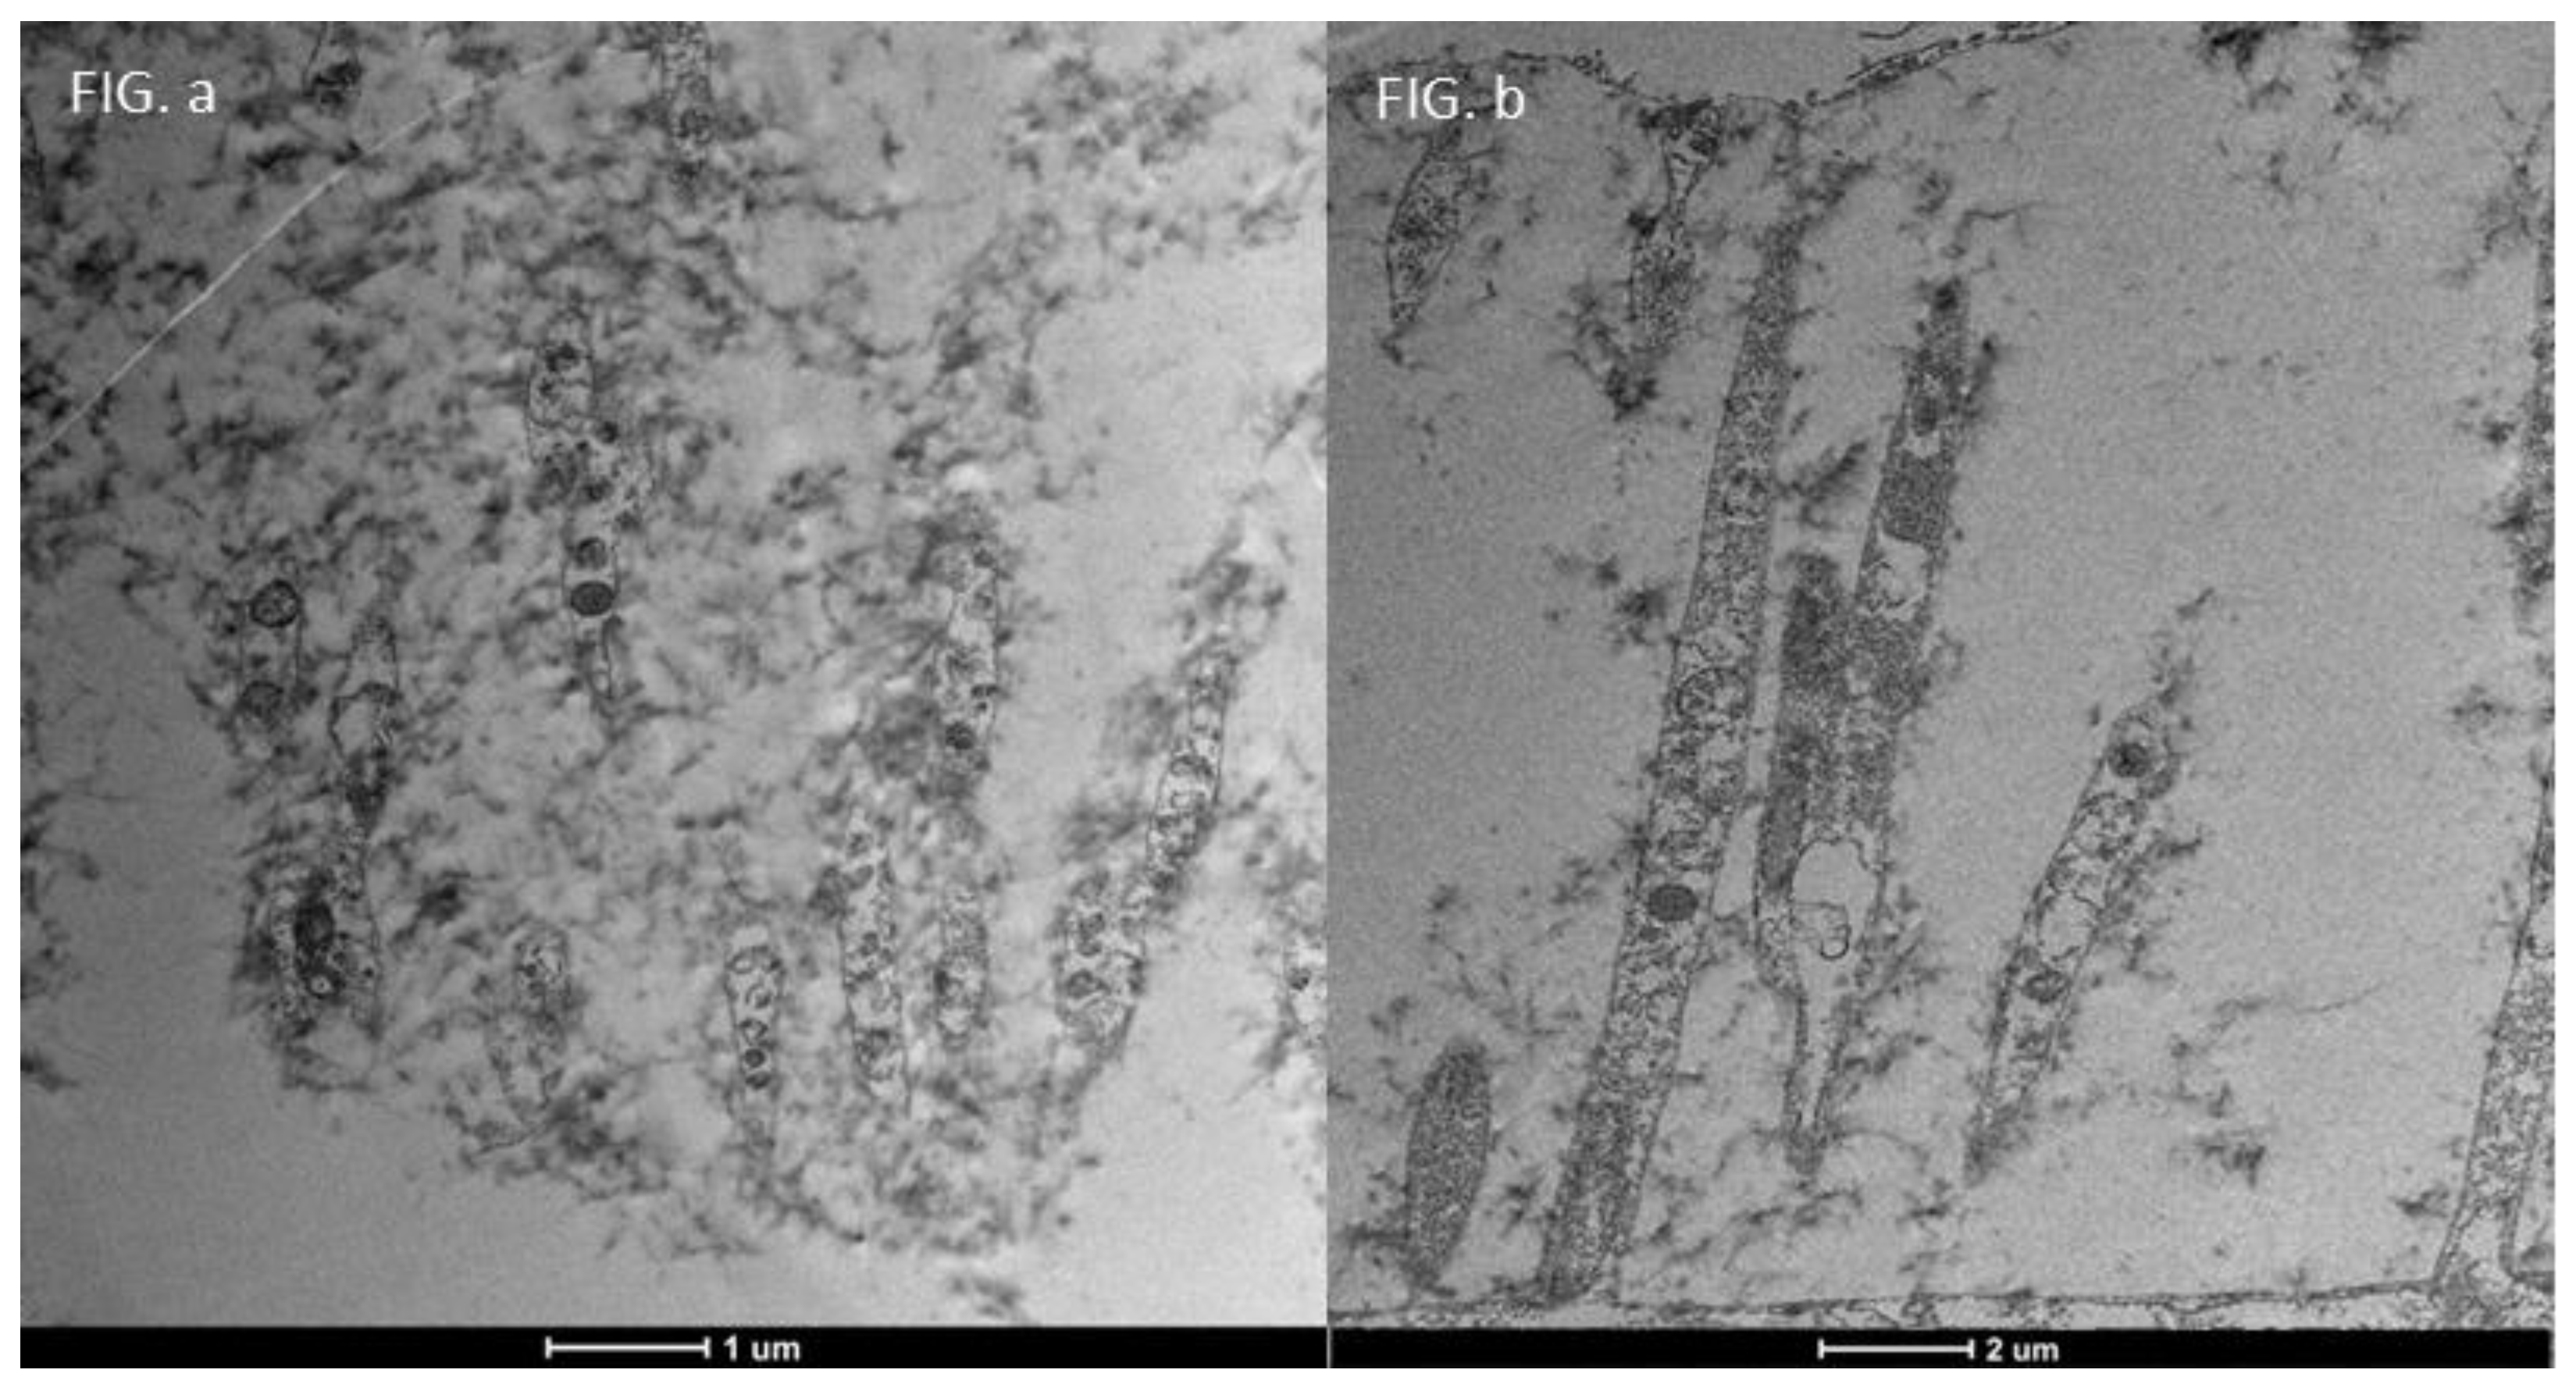

3.6. Glycocalyx Function and Structure

- Composition: Primarily composed of membrane mucins (O-glycosylated glycoproteins rich in serine, threonine, and proline) and glucidic portions of structural membrane molecules (Figure 1).

- Role in Health: In healthy cells, glycoprotein filaments of the glycocalyx contact the mucus layer in the tear film, ensuring corneo-conjunctival wettability and stable tear film formation.

- Role in Disease: In diseased cells, the impaired anchorage of mucus to the epithelium due to altered glycoprotein portions leads to a loss of wettability and prevents stable tear film formation.

| TEM Evaluation Table | ||||

| Grade 0 | Grade 1 | Grade 2 | Grade 3 | Grade 4 |

| Presence of glicocalyx and presence vescicular transport | Reduction of Glicocalyx and presence of vescicular transport | Absence of glicocalyx and reduction of vescicular transport | No glicocalyx, No vescicular transport, Reduction of lenght of microvilli | flattening of the plasma membrane, absence of exchange with the outside |